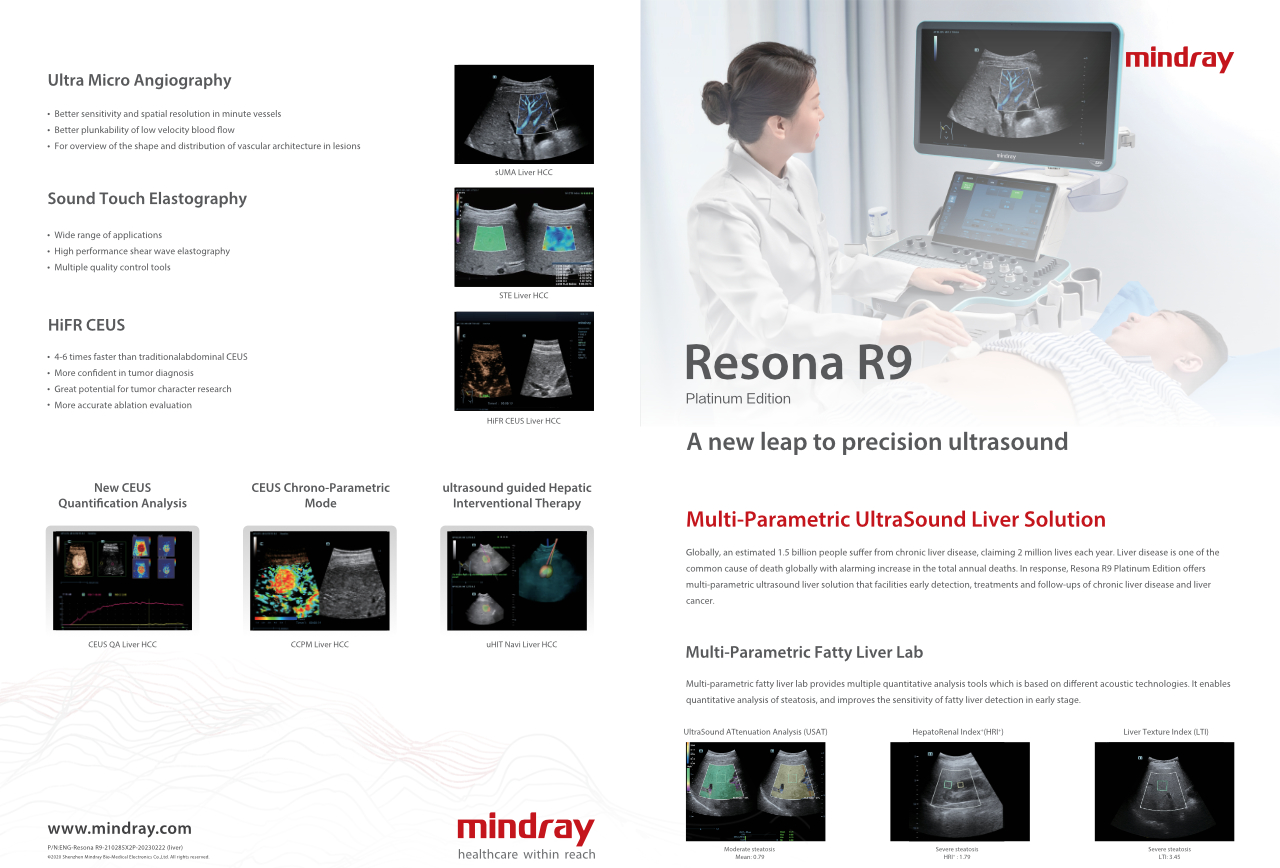

Resona R9 Platinum Edition

Um novo patamar para o ultrassom de precis?o

Integrando uma variedade de ferramentas multiparamûˋtricas inovadoras com um novo nûÙvel de nitidez de imagem, o Resona R9 Platinum Edition proporciona um novo avan?o tanto para a rotina clûÙnica quanto para fins de pesquisa.

Em todo o mundo, estima-se que 1,5 bilh?o de pessoas sofram de doen?a hepûÀtica cr?nica, levando a 2 milh?es de mortes por ano. A doen?a hepûÀtica ûˋ uma das causas mais comuns de morte em todo o mundo, com um aumento alarmante no total de mortes anuais. Em resposta, o Resona R9 Platinum Edition oferece uma solu??o de ultrassom multiparamûˋtrico para o fûÙgado que facilita a detec??o precoce, tratamento e acompanhamento de doen?as hepûÀticas cr?nicas e c?ncer de fûÙgado.